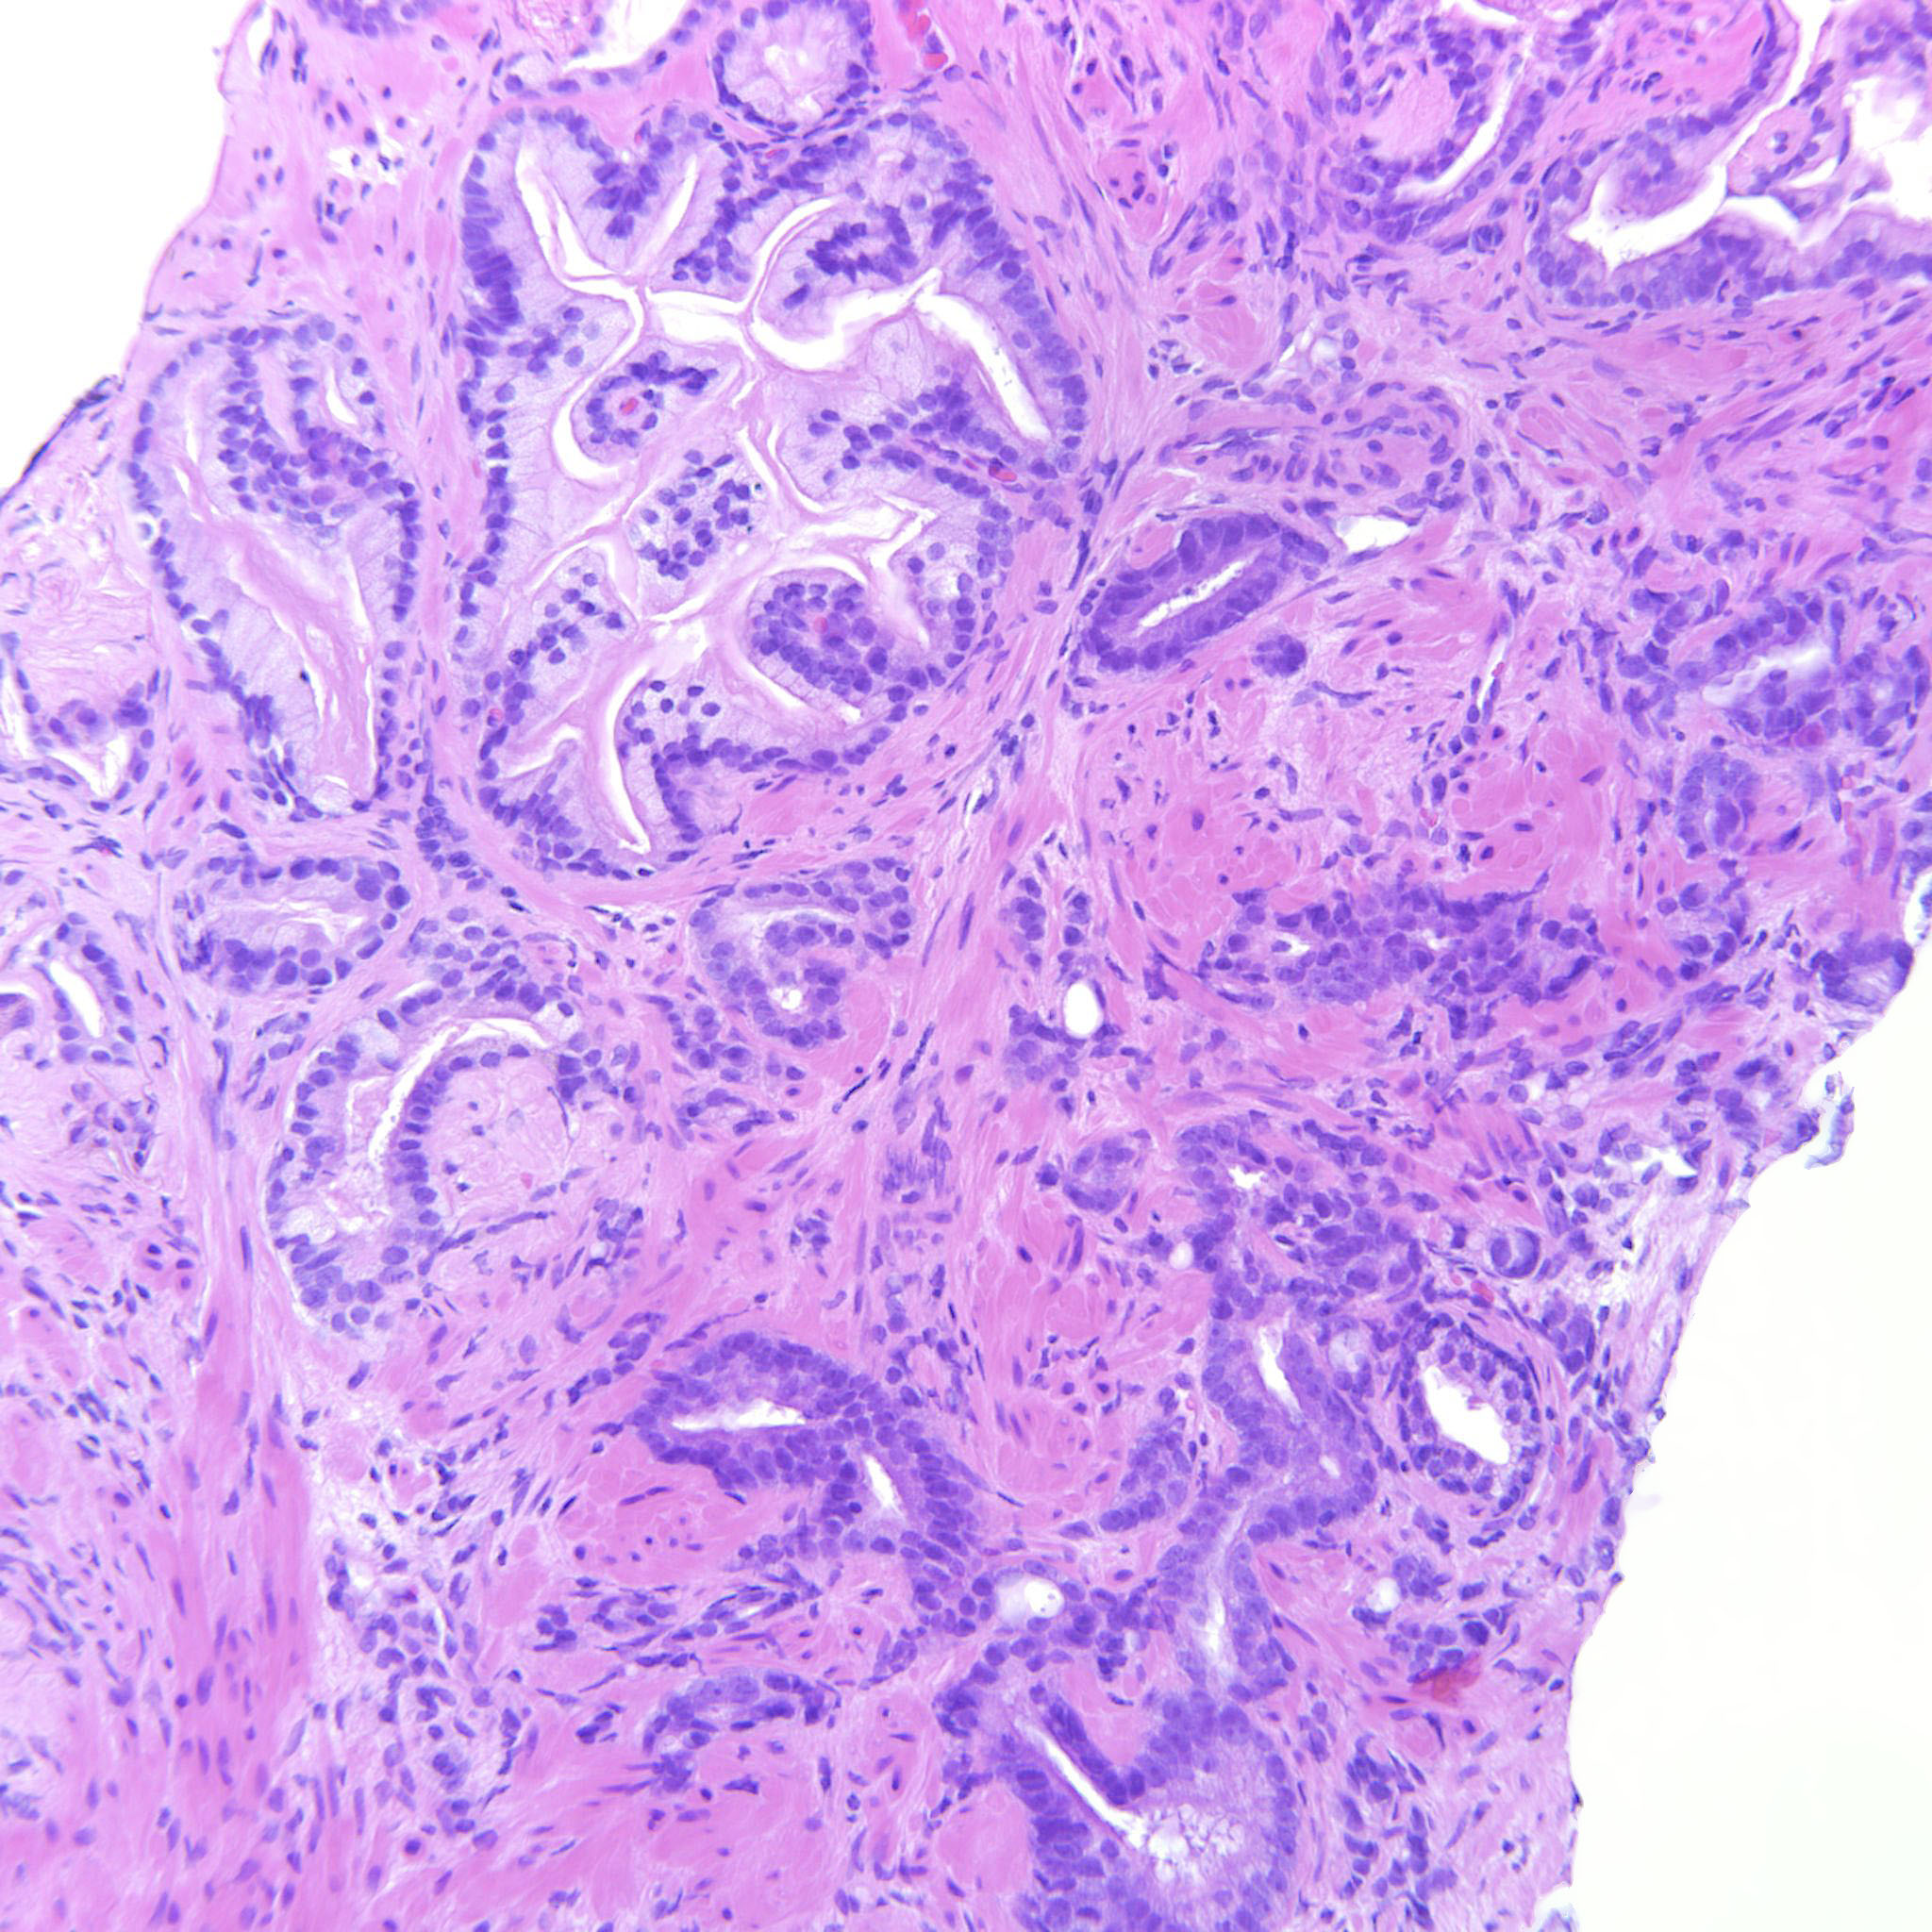

Prostate cancer grading

Case ID: 516